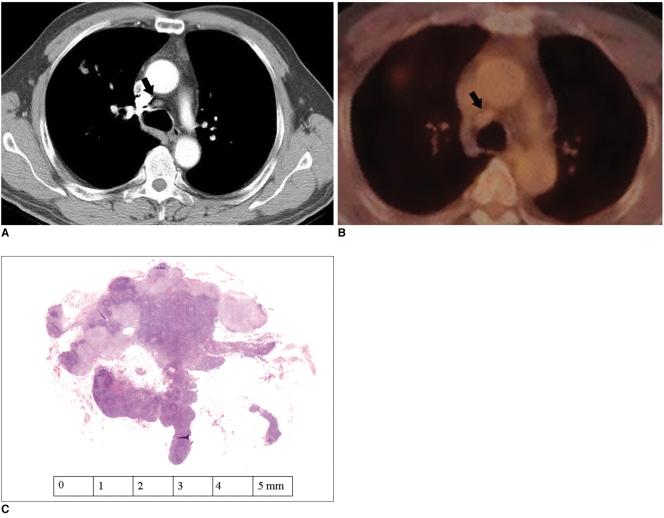

Fluorodeoxyglucose (FDG)-positron emission tomography (PET) is being used more and more to differentiate benign from malignant focal lesions and it has been shown to be more efficacious than conventional chest computed tomography (CT). However, FDG is not a cancer-specific agent, and false positive findings in benign diseases have been reported. Infectious diseases (mycobacterial, fungal, bacterial infection), sarcoidosis, radiation pneumonitis and post-operative surgical conditions have shown intense uptake on PET scan. On the other hand, tumors with low glycolytic activity such as adenomas, bronchioloalveolar carcinomas, carcinoid tumors, low grade lymphomas and small sized tumors have revealed false negative findings on PET scan. Furthermore, in diseases located near the physiologic uptake sites (heart, bladder, kidney, and liver), FDG-PET should be complemented with other imaging modalities to confirm results and to minimize false negative findings. Familiarity with these false positive and negative findings will help radiologists interpret PET scans more accurately and also will help to determine the significance of the findings. In this review, we illustrate false positive and negative findings of PET scan in a variety of diseases.